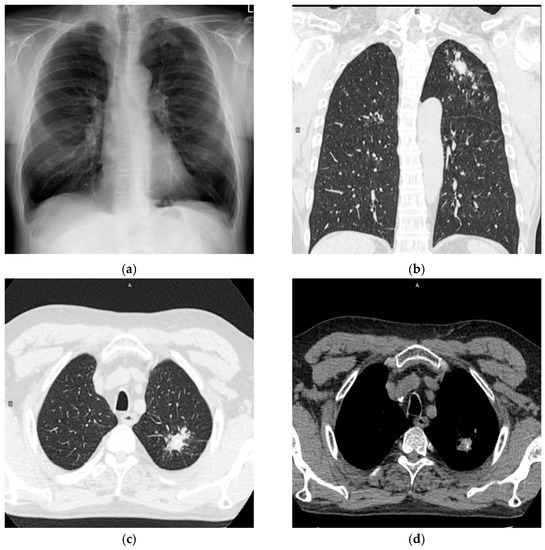

A 62-year-old male was admitted to the Department of Thoracic Surgery of National Tuberculosis and Lung Diseases Research Institute due to a focal lesion localized in the left lung. Irregular shape consolidation in the upper zone of the left lung was found in a chest X-ray (Figure 1a). Chest CT (chest computed tomography) revealed several nodules of various shapes and sizes, with small calcifications, localized in the apicoposterior segment of the left lung. The largest nodule, measuring 28 × 23 mm, had spiculated borders (Figure 1b–d). These findings were ambiguous, requiring differentiation between tuberculosis and neoplasm.

Figure 1.

Chest X-ray and CT (a). Chest X-ray, posteroanterior projection. Irregular shape consolidation in the upper zone of the left lung. (b). Chest CT, lung window, coronal image. Various shape and size lung nodules in the left upper lobe. (c) Chest CT, lung window, axial image. The largest lung nodule with spiculated borders is in the left upper lobe. (d) Chest CT, mediastinal window, axial image. Calcifications in lung nodules.